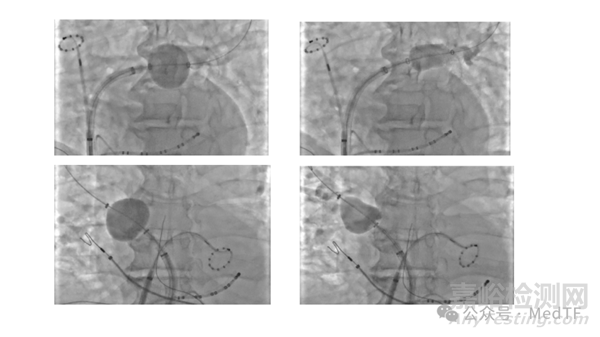

PFBalloon球囊最大的臨床獲益是獨有的超順應(yīng)性,球囊上的柔性電極可以形成特定的弧度和形狀以緊密貼合肺靜脈的開口和前庭,形成環(huán)繞式接觸,保證球囊工作電極大面積有效貼靠肺靜脈等環(huán)形血管組織和心肌等弧面組織,形象地比喻是“ Pulmonary Veins embrace the balloon(肺靜脈包裹著球囊)”。同時,球囊組件本身也具備良好的穩(wěn)定性,在膨脹過程中電極之間不會產(chǎn)生變形和間距不均,并且依然可以調(diào)整不同直徑和方向。在X射線下或者ICE的引導(dǎo)下,可清晰觀察到PFBalloon在不同解剖結(jié)構(gòu)的肺靜脈中的形態(tài),柔性電路組成的消融部件也可以根據(jù)不同的肺靜脈解剖形態(tài)進(jìn)行調(diào)整,以方便電生理醫(yī)生進(jìn)行消融。在X射線或者ICE下,可觀察到PFBalloon球囊順應(yīng)不同肺靜脈的形態(tài),形成了“橄欖形”、“球形”、“南瓜形”,有醫(yī)生戲稱這種消融術(shù)式為“橄欖/球術(shù)式“。

PFBalloon導(dǎo)管PVI消融過程中的“橄欖/球術(shù)式“